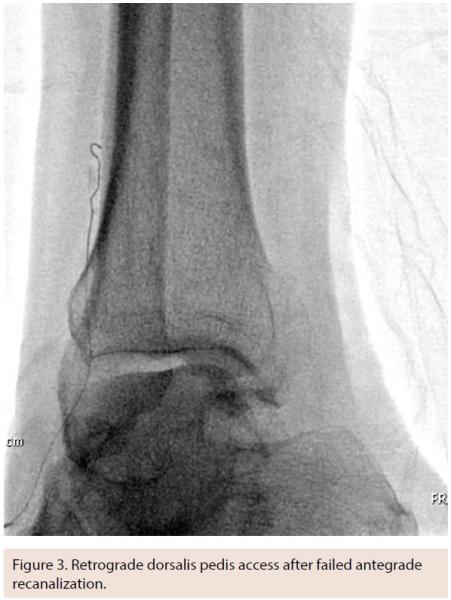

Tibio-pedal artery access (TPAA) is being used with increasing frequency as alternative access to facilitate procedural success in LEAI. This technique is usually employed in the setting of CLI and tibial artery intervention, but may offer potential practical advantages for popliteal artery and even superficial femoral artery (SFA) intervention in unique situations. While others have described TPAA access for intervention for claudication, we have not found it to be necessary in patients with claudication and primarily femoropopliteal disease. In our practice, TPAA is only used in the setting of CLI and in only 5%-10% of those patients. That said, our threshold for moving to an alternative access site with failed antegrade recanalization in tibial arteries has been lowered.

Equally as important to vessel access is an exit strategy that avoids local complications. Acute occlusion, thrombosis, or dissection can be a devastating outcome after a complex tibial intervention. Manual pressure is most commonly used at the level of the foot; however, prolonged balloon inflation is also very commonly used if any kind of wire-reversal technique has been employed. This is the standard approach in our practice.